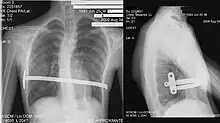

Coupe au scanner.

Le diagnostic est clinique, par l'examen de la déformation thoracique. On peut toutefois proposer la réalisation d'une tomodensitométrie thoracique, permettant le calcul de l'index de Haller, évaluant de manière objective la sévérité de la déformation et permettant de rechercher une compression cardiaque, trachéale ou œsophagienne. Des explorations fonctionnelles respiratoires évaluent l'impact de la déformation sur la fonction pulmonaire, et une épreuve d'effort recherche l'impact sur les capacités d'effort.

Aspect radiologique d'une barre de Nuss en post-opératoire. À noter qu'une scoliose est associée au pectus excavatum.